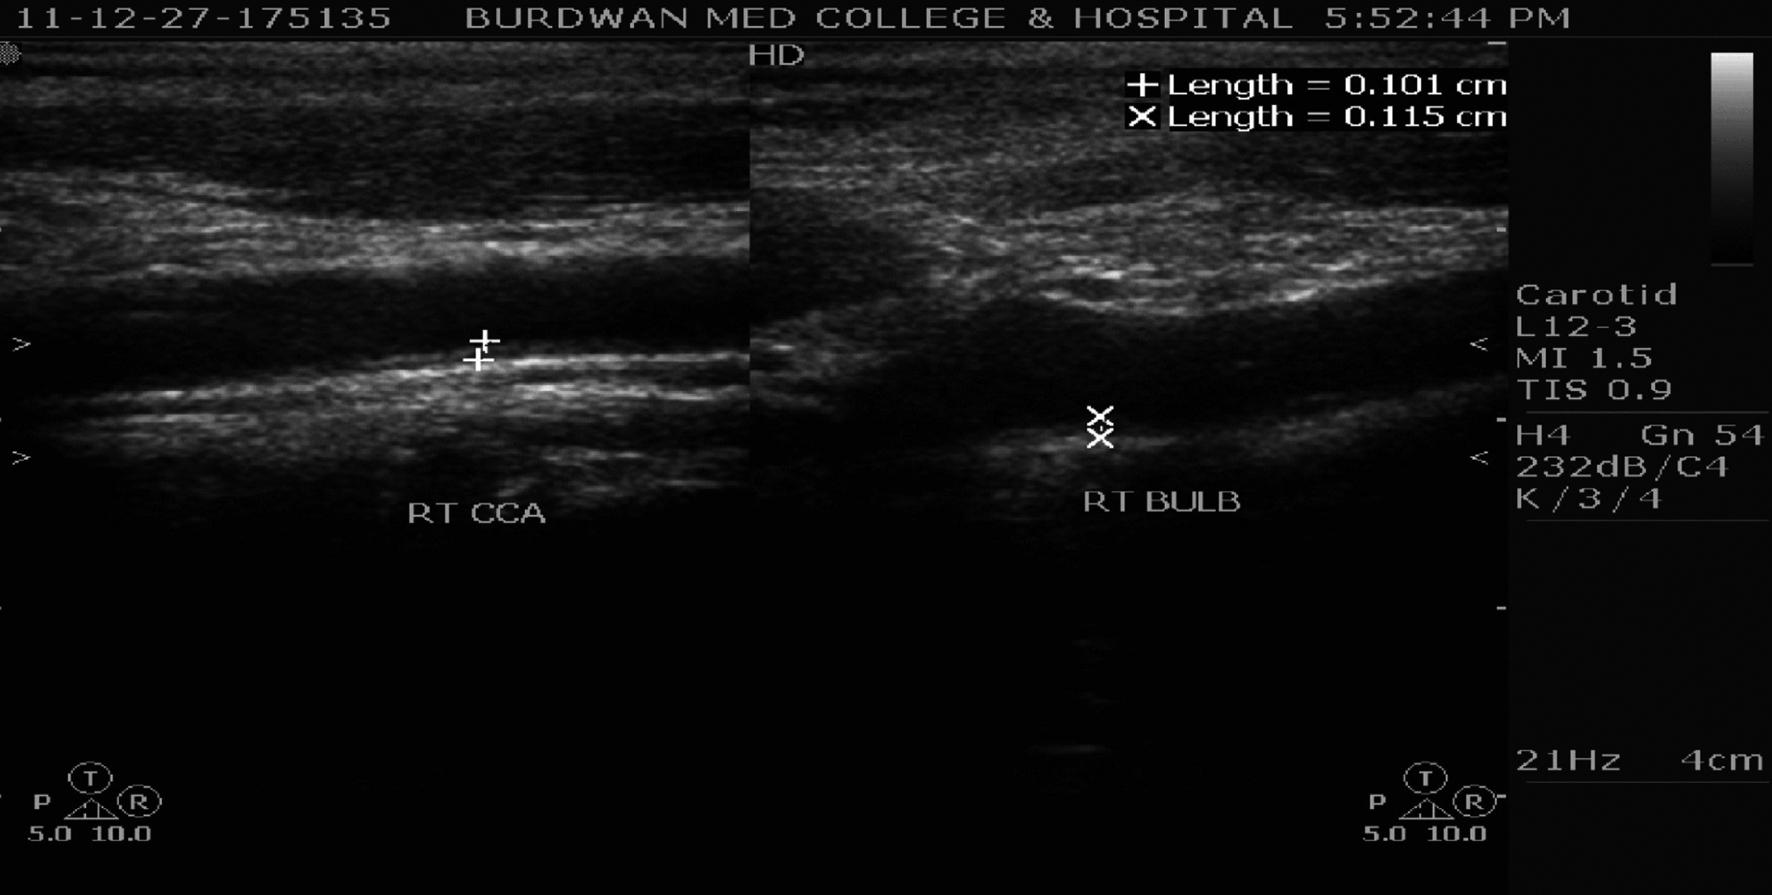

CAIMT was performed with a 7 MHz B-mode ultrasound system (Philips-HD7 Diagnostic Ultrasound System, made in China). The IMT was defined as the distance between the leading edge of the luminal echo to the leading edge of the adventitia of the media, was measured at the diastolic phase (Fig. 1). The B-mode scanning protocol included the scanning of the right and left common carotid arteries (3 cm before the carotid bifurcation), carotid bifurcation, as well as of the internal carotid artery 2 cm distally from the carotid bifurcation [19]. Measurements were always performed in plaque-free arterial segments [20].

![]() Click for large image | Figure 1. Carotid artery intima media thickness at right common carotid artery (RT CCA) and right carotid bifurcation (RT BULB) in a hyperuricemic CRF patient. |